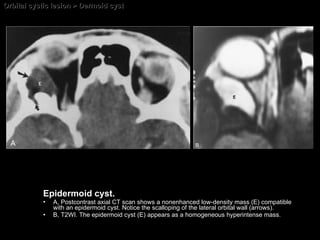

Orbital cystic lesion > Dermoid cyst Epidermoid cyst.  A, Postcontrast axial CT scan shows a nonenhanced low-density mass (E) compatible with an epidermoid cyst. Notice the scalloping of the lateral orbital wall (arrows).  B, T2WI. The epidermoid cyst (E) appears as a homogeneous hyperintense mass.